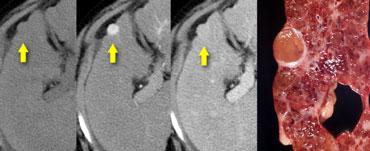

U máu ngấm thuốc nhanh (flash filling) trên thì không tiêm, thì động mạch và thì tĩnh mạch cửa. Lưu ý tỷ trọng tương đương hồ máu.

Các u máu nhỏ có thể biểu hiện ngấm thuốc đồng nhất nhanh chóng (‘flash filling’).

HCC nhỏ và di căn tăng sinh mạch có thể bắt chước u máu nhỏ vì tất cả đều biểu hiện ngấm thuốc đồng nhất trong thì động mạch.

Bằng cách quan sát các thì chụp khác để xem liệu các vùng ngấm thuốc có tương đương hồ máu hay không, thông thường có thể phân biệt được các tổn thương này.